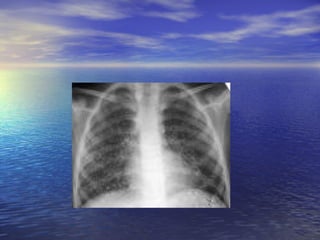

This is  a chest radiograph taken after therapy of a patient with tuberculosis.